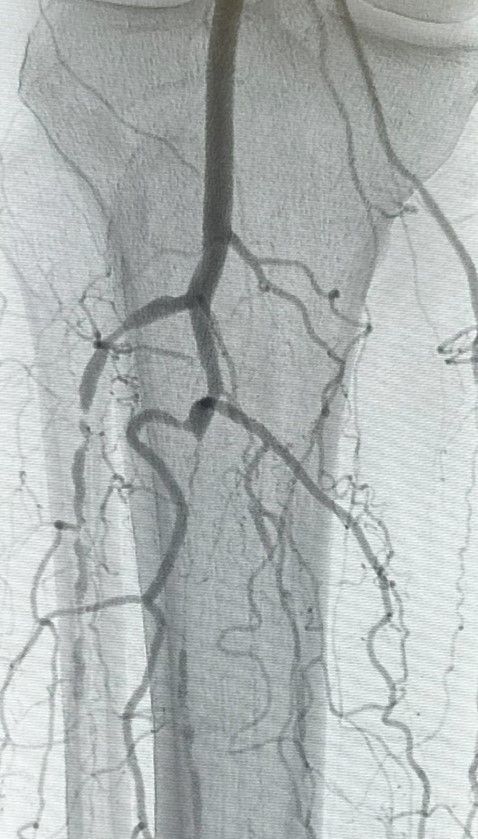

At our center, you'll find physicians with exceptional skills in diagnosing and treating vascular conditions. Our approach combines detailed care with innovative therapies, all aimed at enhancing your life by addressing arterial and venous diseases with precision and compassion.

Dive into advanced care with our Surgical Center, where we confront vascular challenges using the latest advancements in technology. Our procedures are designed to be minimally invasive, promoting quicker healing and enduring health, handled with utmost precision and attention.